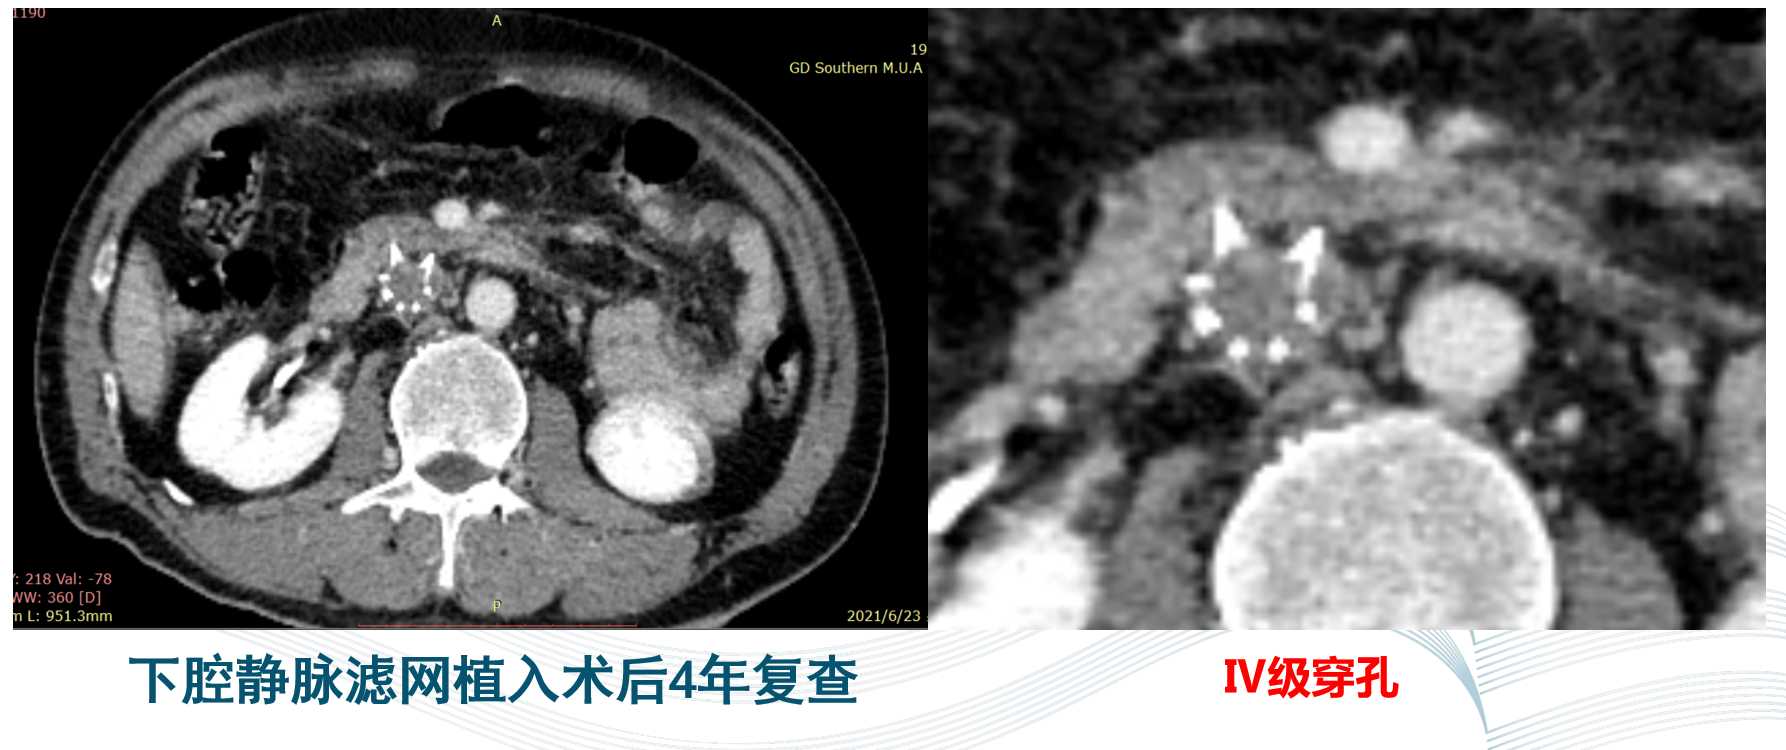

长期口服利伐沙班(10mg QD),期间反复出血牙龈出血及尿血表现,调整抗凝方案为:利伐沙班5mg+阿司匹林肠溶片100mg后,牙龈出血稍改善;术后4年,患者复查提示下腔静脉滤器已经穿透十二指肠壁,达到Ⅳ级穿孔。

目前患者存在上消化道大出血风险,需要积极处理,预防下腔静脉与十二指肠瘘的发生,与患者及其家属沟通后,取得患者的充分信任 ,拟全麻下行开腹手术,下腔静脉切开取滤网手术(注:由于患者前期植入的滤网为梭型,非伞型,无法通过腹腔镜完成)。